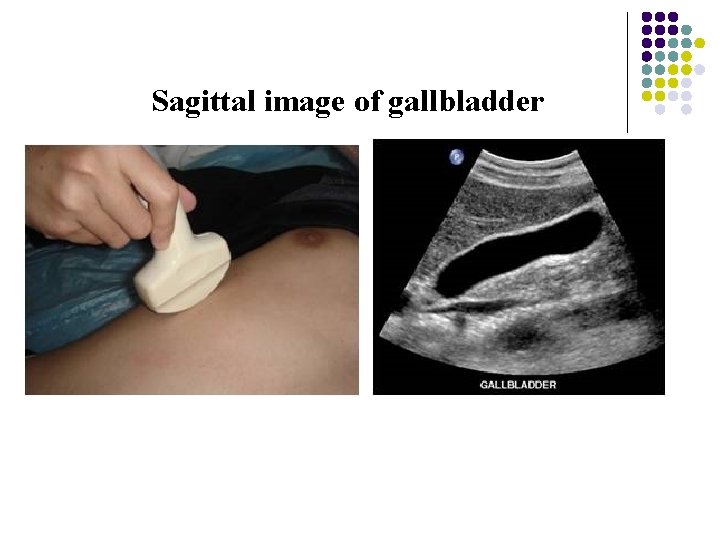

Sagittal image of gallbladder

Gallbladder and Biliary System Normal size of gallbladder: 7~9 cm in length ; 3~4 cm in width; Wall thickness : 2~3 mm l Normal size of bile ducts : right /left intrahepatic duct just to proximal CHD: 2 -3 mm ; CBD: ≥ 8 mm =dilated l